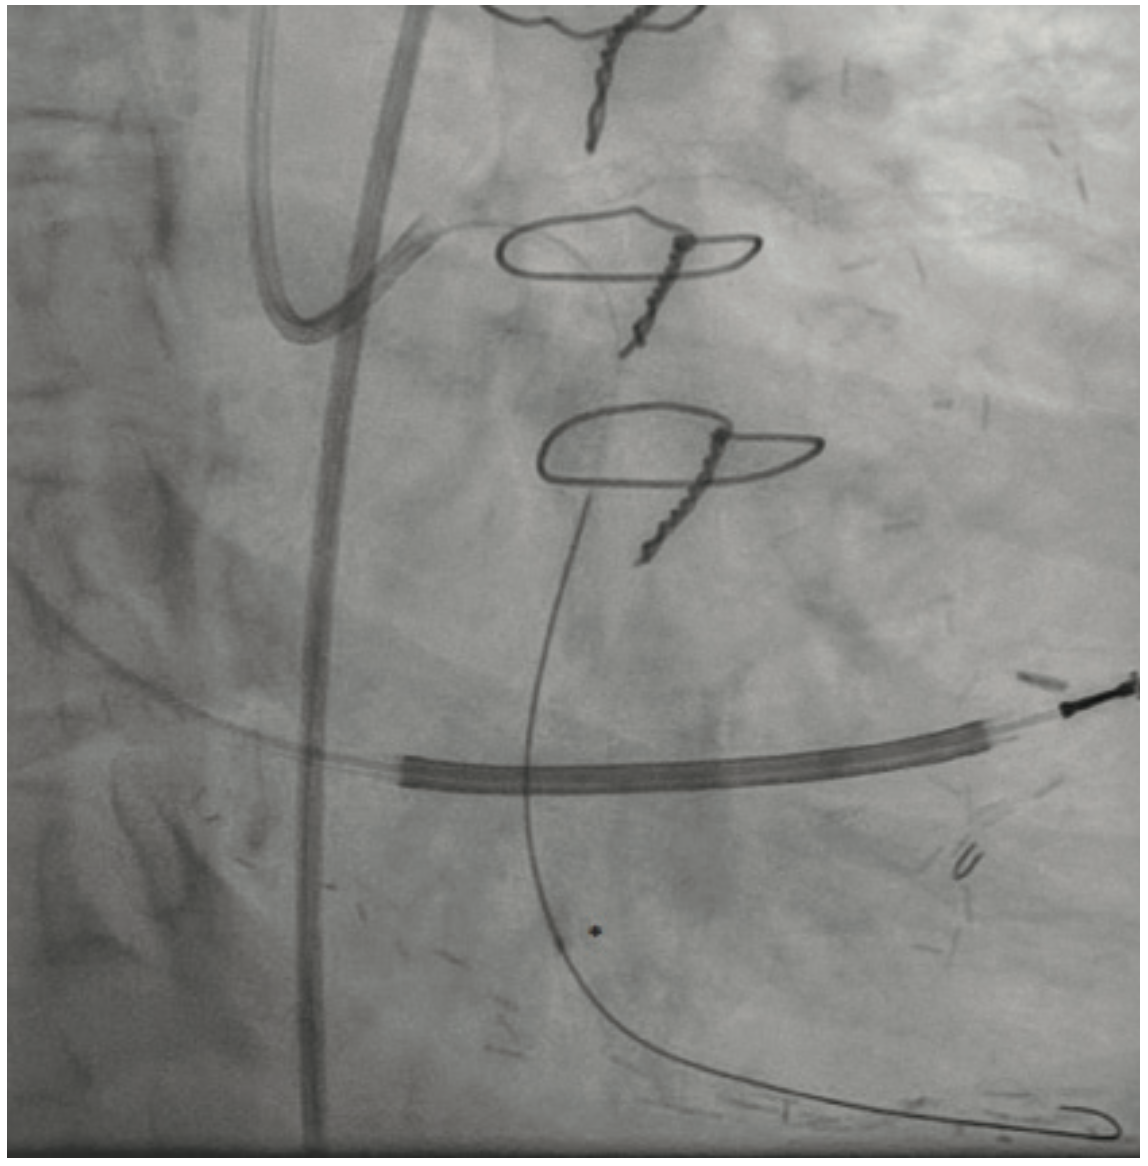

The ipsilateral collaterals to the culprit vessel precluded the need for dual access, and a 6 French (F) VL3 guide catheter (Boston Scientific) was placed via the right femoral access. A Turnpike LP microcatheter (Teleflex) was used for wire support and exchanges. Initial crossing attempts with Runthrough NS Extra Floppy (Terumo Interventional Systems) and Fielder XT-a (Asahi Intecc) wires were unsuccessful. The lesion was crossed successfully with a MiracleBros 6 (Asahi Intecc) wire and the tip was clearly visualized in the remains of the jump graft (Figure 4). Attempts to then cross the lesion with Turnpike LP and Turnpike Gold microcatheters (Teleflex) for lesion dilation and possible wire exchange were unsuccessful despite very good guide support (Figure 5).